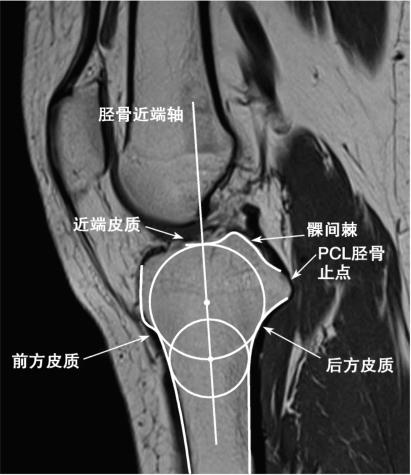

图5-5 确定胫骨近端轴线

选取平面需满足以下三个要求:①可见髁间棘;②可见后交叉韧带止点;③胫骨近端呈倒凸字形。画一圆,与胫骨近端、前后侧皮质相切,在该圆的圆周上找一点作为圆心,画一个与前后侧皮质相切的圆,两圆圆心的连线为轴线。